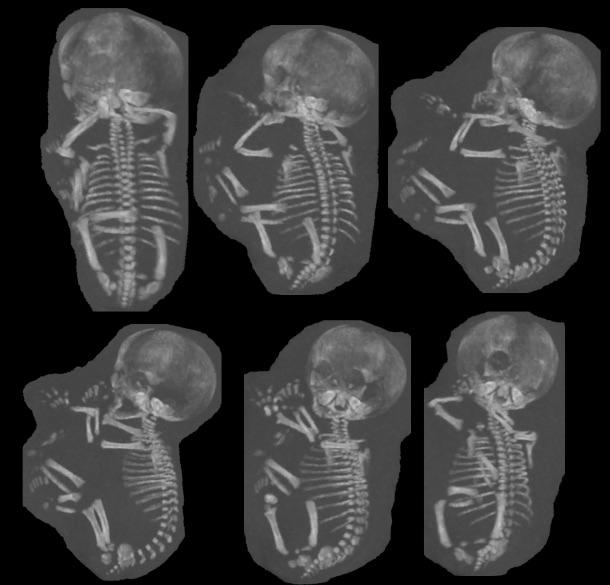

【期間限定!最安値挑戦】 症例に学ぶ新生児X線診断 語学+参考書の詳細情報

症例に学ぶ新生児X線診断。新版胸部単純X線診断: 画像の成り立ちと読影の進め方 | 林 邦昭。目でみる症例 ニューモシスチス肺炎 (臨床雑誌内科 95巻4号。

症例に学ぶ新生児X線診断

症例に学ぶ新生児X線診断